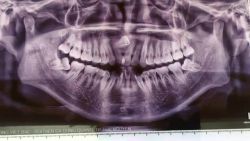

Khi răng khôn (răng số 8 – răng hàm lớn thứ 3) không có đủ chỗ để mọc, nó sẽ bị chèn ép và kẹt ở bên dưới lợi, đôi khi là ở một góc nào đó. Răng khôn mọc kẹt là tình trạng tương đối phổ biến, có thể gây đau, nhiễm trùng, mọc nghiêng vẹo, mọc chen chúc, u nang răng, sâu răng, khó há miệng và đau hàm. Nếu răng khôn gây ra (hoặc sẽ gây ra) các vấn đề trên, nha sĩ sẽ khuyên bạn nhổ bỏ nó.

Một số chuyên gia khuyên bệnh nhân không nên nhổ răng khôn bởi vì họ dựa vào thăm khám lâm sàng và chụp X-quang răng. Kết quả cho thấy răng khôn “mọc khôn”, không có bệnh hoặc không tiềm ẩn nguy cơ gây ảnh hưởng xấu đến các răng khác, nên các chuyên gia chỉ định không cần thiết nhổ răng khôn.